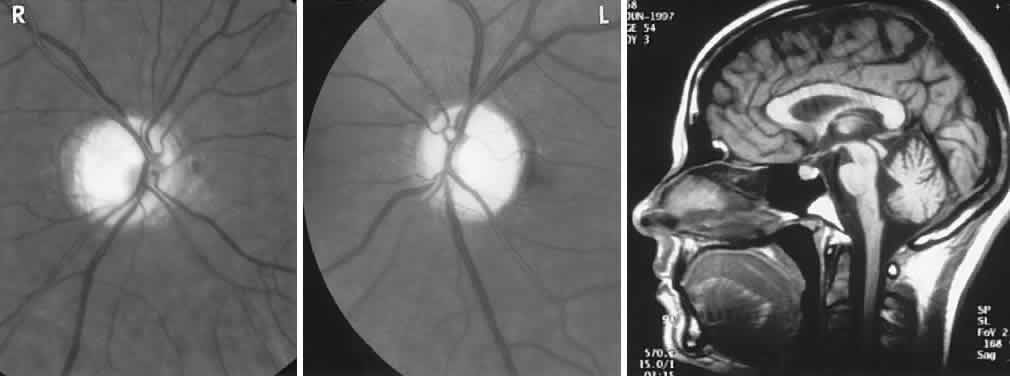

Fig. 10. Tuberous sclerosis. Retinal astrocytic hamartomas in epipapillary, parapapillary, and peripheral sites. A. Superficial translucent lesions through which retinal vessels may be seen. B. Peripheral calcified “mulberry” lesion. C. Cutaneous stigmata include facial fibroma (“adenoma sebaceum”) and periungual fibroma of the toes and fingers.

Color Plate 5-1. A. Myelinated nerve fibers. Retina is white, opaque, with feathered edges. B. Calcified astrocytic hamartoma of retinal nerve fiber layer in tuberous sclerosis. C. Hypoplasia of the optic nerve. Disk is small and with pigment rim and surrounding paler ring. Disk vessels appear disproportionately large. D. Inferior crescent. Disk is small and horizontally oval with scleral crescent at lower border. Contiguous inferior fundus sector is hypopigmented and appears albinotic; foveal reflext is indistinct. E. Pseudopapilledema; congenital elevated disk (compare with true papilledema, F). Note absence of central cup, vessels arise at disk apex. Vascular anomalies include excessive number of major disk vessels and multiple bifurcations. Nerve fiber layer does not obscure vessels at disk margins. F. Chronic moderate papilledema (compare with pseudopapilledema in E.) Note retention of central cup, flame hemorrhage at superior border, absence of anomalous vessel pattern, small arterioles are obscured in nerve fiber layer.

The retinal hamartomas are said to occur in approximately half of patients with tuberous sclerosis. Though rarely symptomatic themselves, they are of great help in establishing diagnosis in the setting of seizures, facial angiofibromas and variable mental retardation. Seizures and EEG abnormalities are present in 80% to 90%, adenoma sebaceum in 80%, mental retardation in 60%, intracranial calcifications in 50%, as well as cardiac rhabdomyomas or hamartomas.147 Because of ventricular obstruction by giant cell astrocytomas, papilledema may develop and consequently visual loss.148 On rare occasions abnormal capillaries on optic disc astrocytomas may abruptly alter vision because of intravitreal hemorrhage.149 Familial occurrence in first-degree relatives should be sought, but some 60% of cases arise as new mutations.